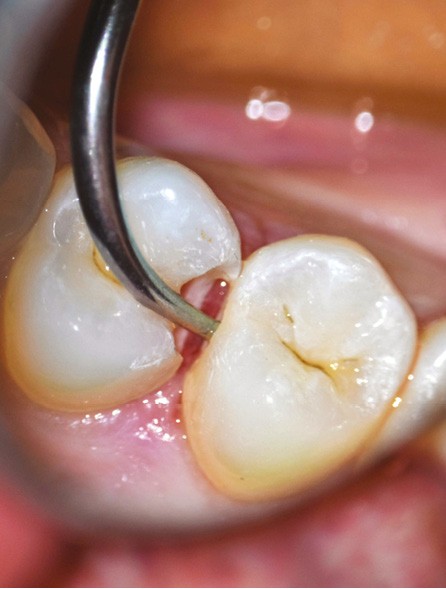

• Traitement invasif a minima : il concerne les lésions carieuses cavitaires ou non avec atteinte dentinaire (à partir du 1/3 moyen dentinaire), soit ICDAS 3 à 6. Dans ce cas, la priorité est de préserver la dent d’une effraction pulpaire éventuelle (recommandations de l’ESE) [4]. C’est pourquoi, lors du traitement de lésions carieuses profondes (ICDAS 4 à 6), il faut dans tous les cas réaliser une éviction sélective, réaliser une préparation a minima (favoriser les préparations de type fente (« slot ») ou tunnel lorsque l’indication se pose) et utiliser un matériau de restauration de choix, soit composite, soit un ciment verre ionomère (CVI), soit des matériaux à base de silicate de calcium ou encore les nouveaux composites enrichis en minéraux (fig. 7 à 9). Ces préparations a minima peuvent être réalisées avec des fraises de petits diamètres (fig. 10 et 11).